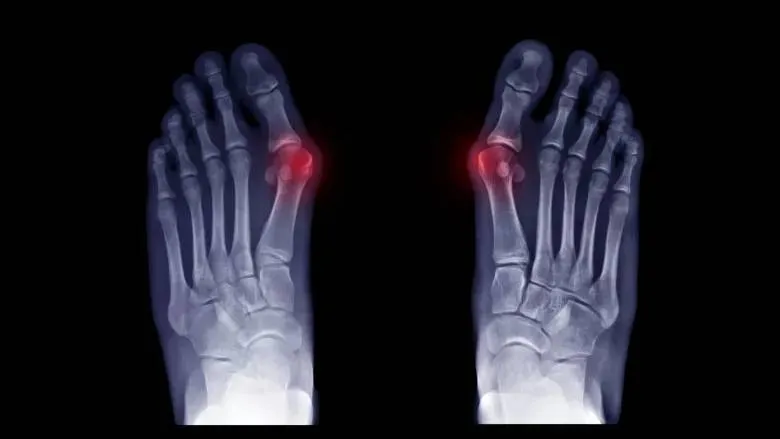

How can you recognize a bunion problem?

Patients often come with forefoot pain combined with a change in toe position or limited toe mobility. X-ray imaging helps determine the severity of the condition. A frequent issue is reduced physical activity, which can further aggravate the deformity.

Modern methods use a procedure called corrective osteotomy, which involves shifting the bones to straighten the toe and eliminate the cause of the deformity. Unlike older techniques, which focused only on removing bone growths, the risk of recurrence is now significantly reduced.